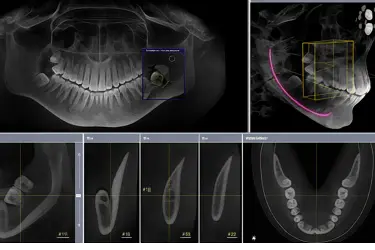

TAC completo de ambas arcadas

Proporciona una imagen 3D completa de las dos arcadas, maxilar superior e inferior, junto con los tejidos y estructuras óseas adyacentes.

Este examen ofrece una visión global de toda la cavidad oral, facilitando la planificación integral de tratamientos que combinan prótesis, ortodoncia o implantes en ambas arcadas.

Permite al ortodoncista examinar la alineación y posición exacta de los dientes y huesos para diseñar un plan de tratamiento más preciso.

Además, el TAC dental facilita la detección de dientes retenidos, anomalías en la erupción y asimetrías óseas.